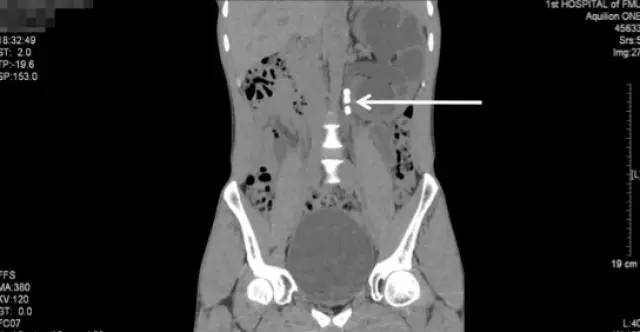

入院后进一步行泌尿系CT平扫+三维重建

(白色箭头提示的就是多发的残留结石)

泌尿系CT:红箭头示左肾重度积水;白箭头示多发结石

白色箭头所指就是引起梗阻的掉到输尿管的结石

CT三维重建图像可见左肾明显增大、扩张积水、多发结石